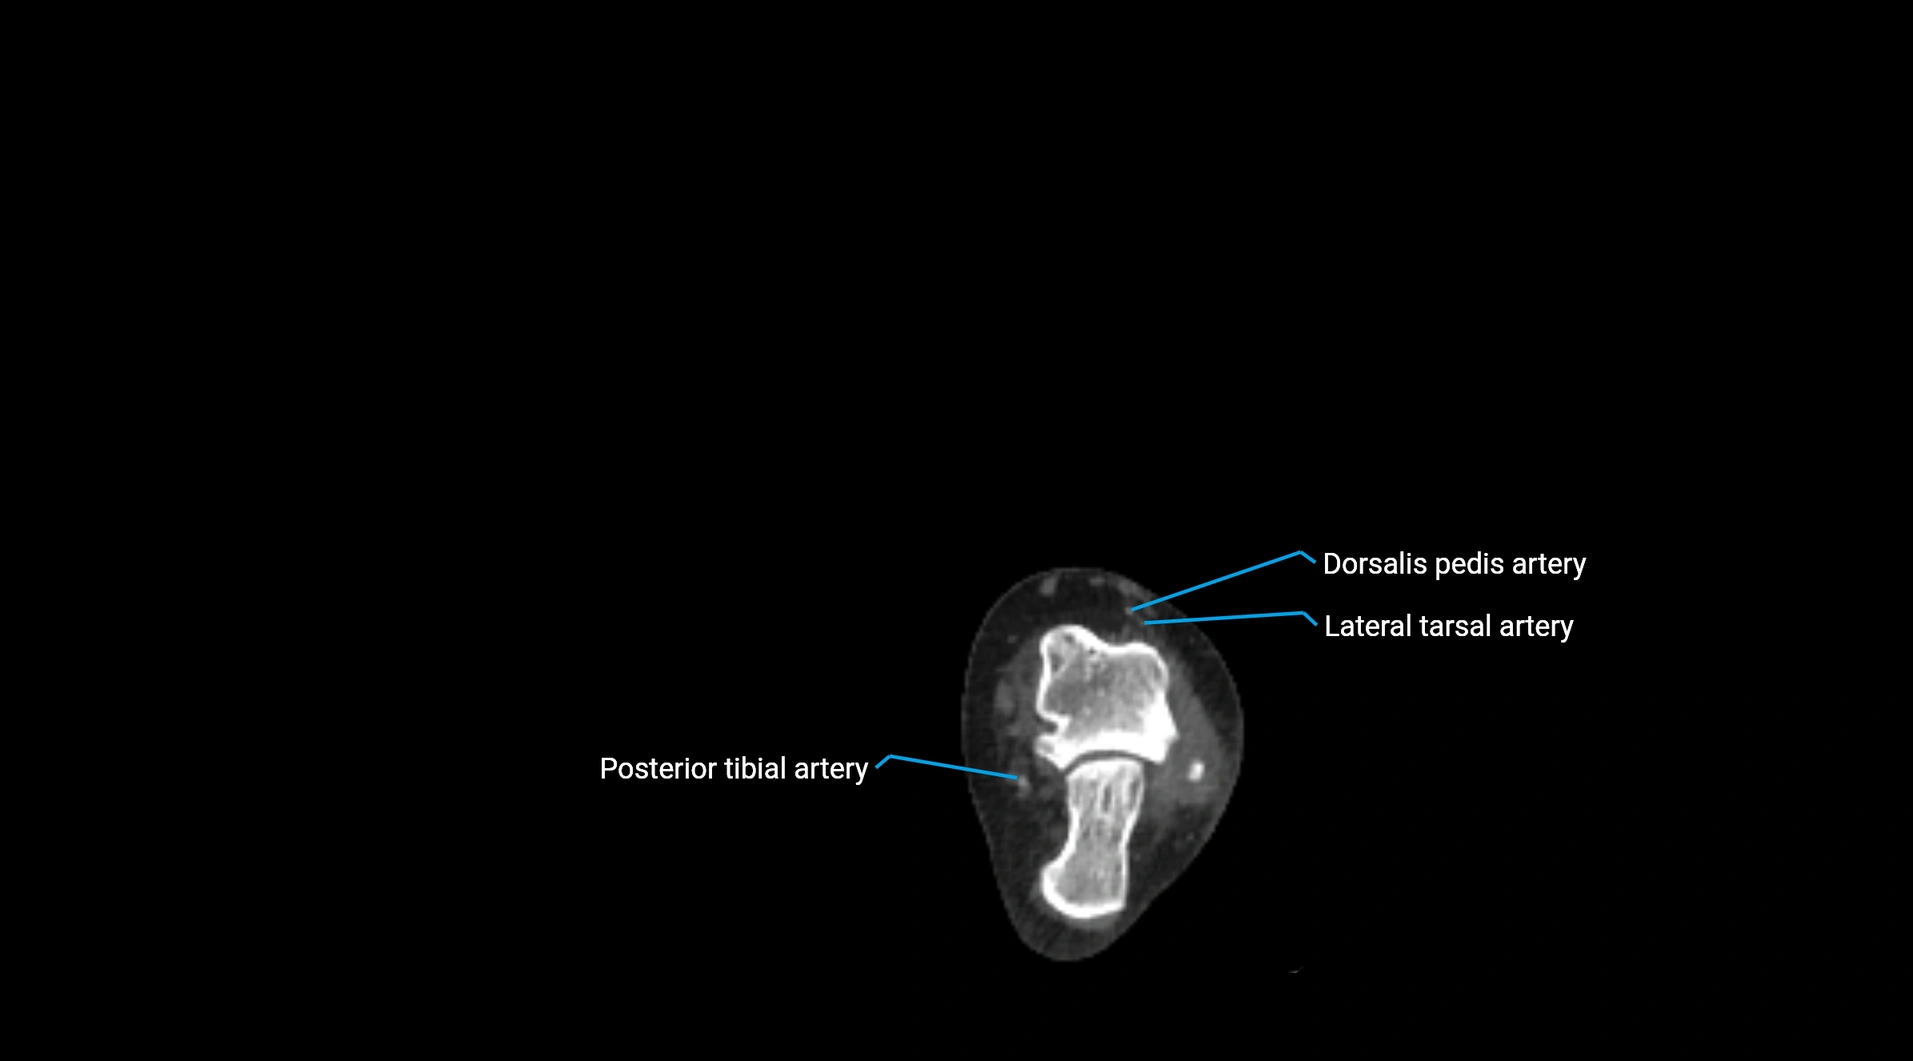

CT images

image